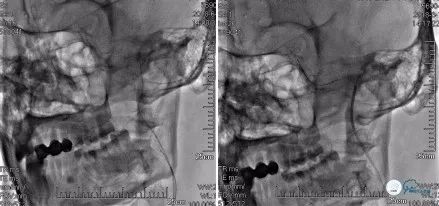

在局麻下右股动脉置入8F动脉鞘,沿常规泥鳅导丝携带5F多功能导管、8F球囊导管在路径图下送至左颈内动脉开口处,造影提示:左颈内动脉C1段可见不规则残端,考虑血栓形成可能(图7)

将球囊导管固定于左颈总动脉远端,充盈球囊阻断前向血流(图8)

并反复抽吸多功能导管,抽出一2*3mm致密斑块(图9)

抽瘪球囊,再次多功能导管手推造影:未见明显游离血栓影,仍无明显前向血流(图10)